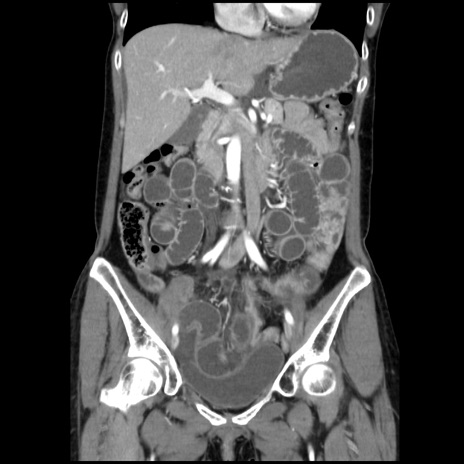

横断像

【症例】40歳代 女性

【主訴】上腹部痛、嘔気・嘔吐

【現病歴】約9時間前頃から急に上腹部痛、嘔気、嘔吐が出現。改善しないため救急要請。

【既往歴】子宮頚癌(広汎子宮全摘術、放射線療法)、腸閉塞

【身体所見】腹部:平坦、軟、腸雑音亢進、上腹部を中心に腹部全体に圧痛あり。

【データ】WBC 8400、CRP 0.03